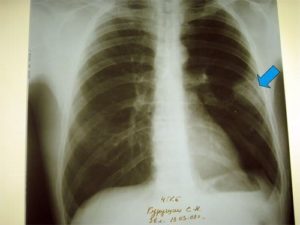

Для обнаружения легочных заболеваний в первую очередь используется флюорография. Эту процедуру необходимо проводить ежегодно, в основном она направлена на выявление ранней стадии туберкулеза. Однако опытный рентгенолог может выявить на снимке образовавшиеся плевральные спайки, которые выглядят тенями. Причем форма их не меняется в зависимости от вдоха и выдоха.

При необходимости дополнительно назначается рентген. Как правило, спайки располагаются в нижней части легкого. При этом будет более темная картинка, а также может быть частичная деформация грудной клетки и диафрагмы.

Определить наличие спаек в легких можно при помощи флюорографии. Этот метод исследования является наиболее достоверным. Дополнительно могут назначить рентген легких. Врач определяет наличие спаек по характерным темным пятнам, которые видны при получении рентгеновского снимка. Изменения могут также наблюдаться в диафрагме — она становится менее подвижной.

Самым распространенным методом диагностики легких является – флюорография. Но если врач подозревает, что у пациента есть спайки, то больной отправляется на рентген. По рентгеновскому снимку распознать синехию можно по мутным темным пятнам. Она выглядит, как теневое затемнение и неподвижна при вдохе и выдохе.

Плевродиафрагмальная спайка на снимке рентгена

Иногда выявляется деформация грудной клетки и диафрагмы. Чаще всего спаечный процесс отмечается в нижней части легкого. Такой вид спаек – плевродиафрагмальный, а вид спаек в верхней части – плевроапикальный.